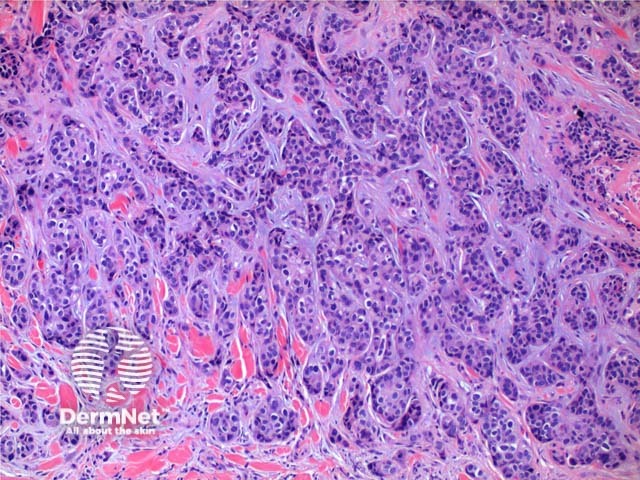

The histology of metastatic adenocarcinoma may show a number of patterns. Low power view frequently shows a poorly circumscribed infiltrating tumour centred on the dermis (Figure 1). Cords and nodules of atypical epithelial cells can be seen dissecting between collagen bundles (Figure 2). These may show evidence of duct or gland formation (Figure 3), and may be set in a mucinous stroma (Figure 4). Vascular and lymphatic permeation may be evident in the telangiectoides and erysipeloides variants of breast metastases.

Figure 2